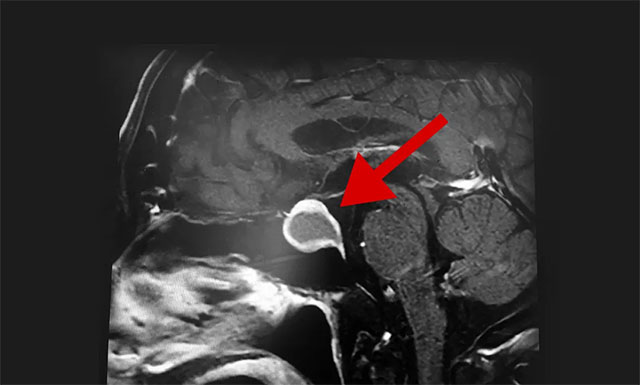

随后,患者进行了头部鞍区MRI平扫+增强,结果显示:蝶鞍部显著扩大,鞍区见一不规则肿块,大小约为2厘米X2.7厘米X1.9厘米,病变向鞍上生长,突入鞍上池,推移视交叉,向下生长,鞍底受压变薄,与右侧海绵窦部分解剖结果分界不清。

▲ 影像显示,肿瘤已严重压迫患者视神经

根据患者检查结果,潘仁龙主任介绍,患者之所以视物模糊就是因为垂体肿瘤向鞍上生长,突入鞍上池,压迫到视神经传导物,而使得患者视物范围变小,颞侧、鼻侧视野缺损,表现为进行性视力下降、突然头痛并视力下降。一般1-3cm的大腺瘤或大于3cm的巨大腺瘤,都会引起不同程度的视力问题。